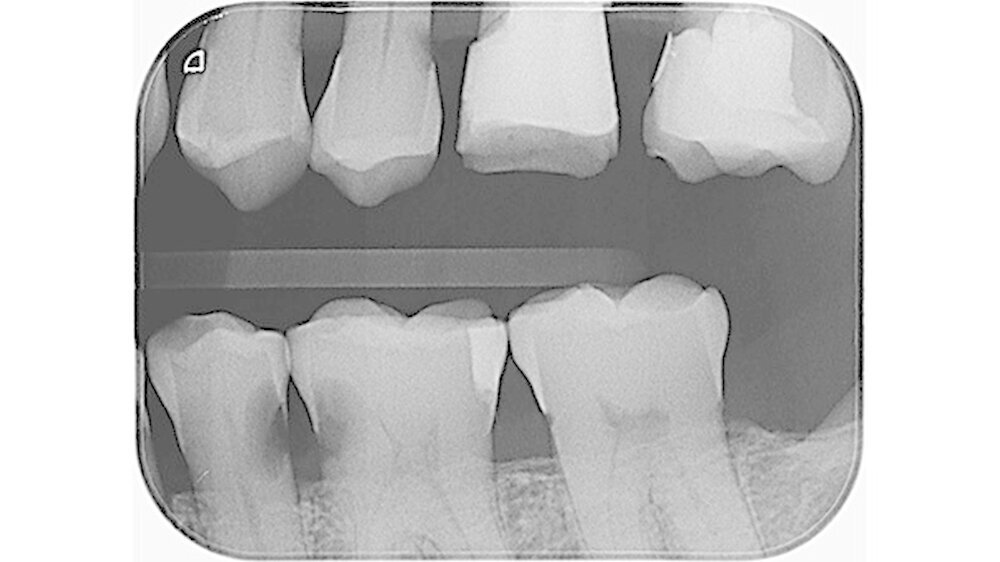

In der aktuellen Deutschen Mundgesundheitsstudie (DMS V) konnte gezeigt werden, dass insbesondere Zähne von pflegebedürftigen Senioren häufig Wurzelkaries aufweisen. Da Wurzelkariesläsionen in unzugänglichen Bereichen wie Approximalräumen schwer zu therapieren sind (Abbildung 2) und die Therapieoptionen bei pflegebedürftigen Patienten meist eingeschränkt sind, ist es von großer Bedeutung, der Entstehung von Wurzelkaries bei Senioren vorzubeugen. Daher war es das Ziel unserer Untersuchung, den Effekt von unterschiedlichen kariesprophylaktischen Substanzen in verschiedenen Darreichungsformen (als Lack oder Spülung) auf die Entstehung von Wurzelkaries in einem kariogenen Biofilmmodell zu untersuchen.